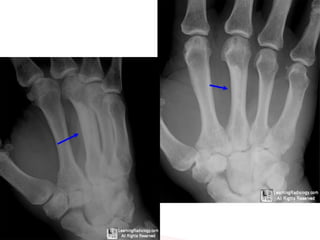

It has a predilection for long bones of the limbs ,it can be seen

almost anywhere

Hands and feet are not infrequently involved ,and involvement of the

axial skeleton is rare

Sclerotic lesions of cortical bones, usually in the diaphysis,

that resemble “candle-wax-dripping”

Cortical hyperostosis with an undulating appearance usually

affecting one side of a bone

Soft tissue lesions that may calcify (Adjacent to involved bone)

May grow to compress nerves